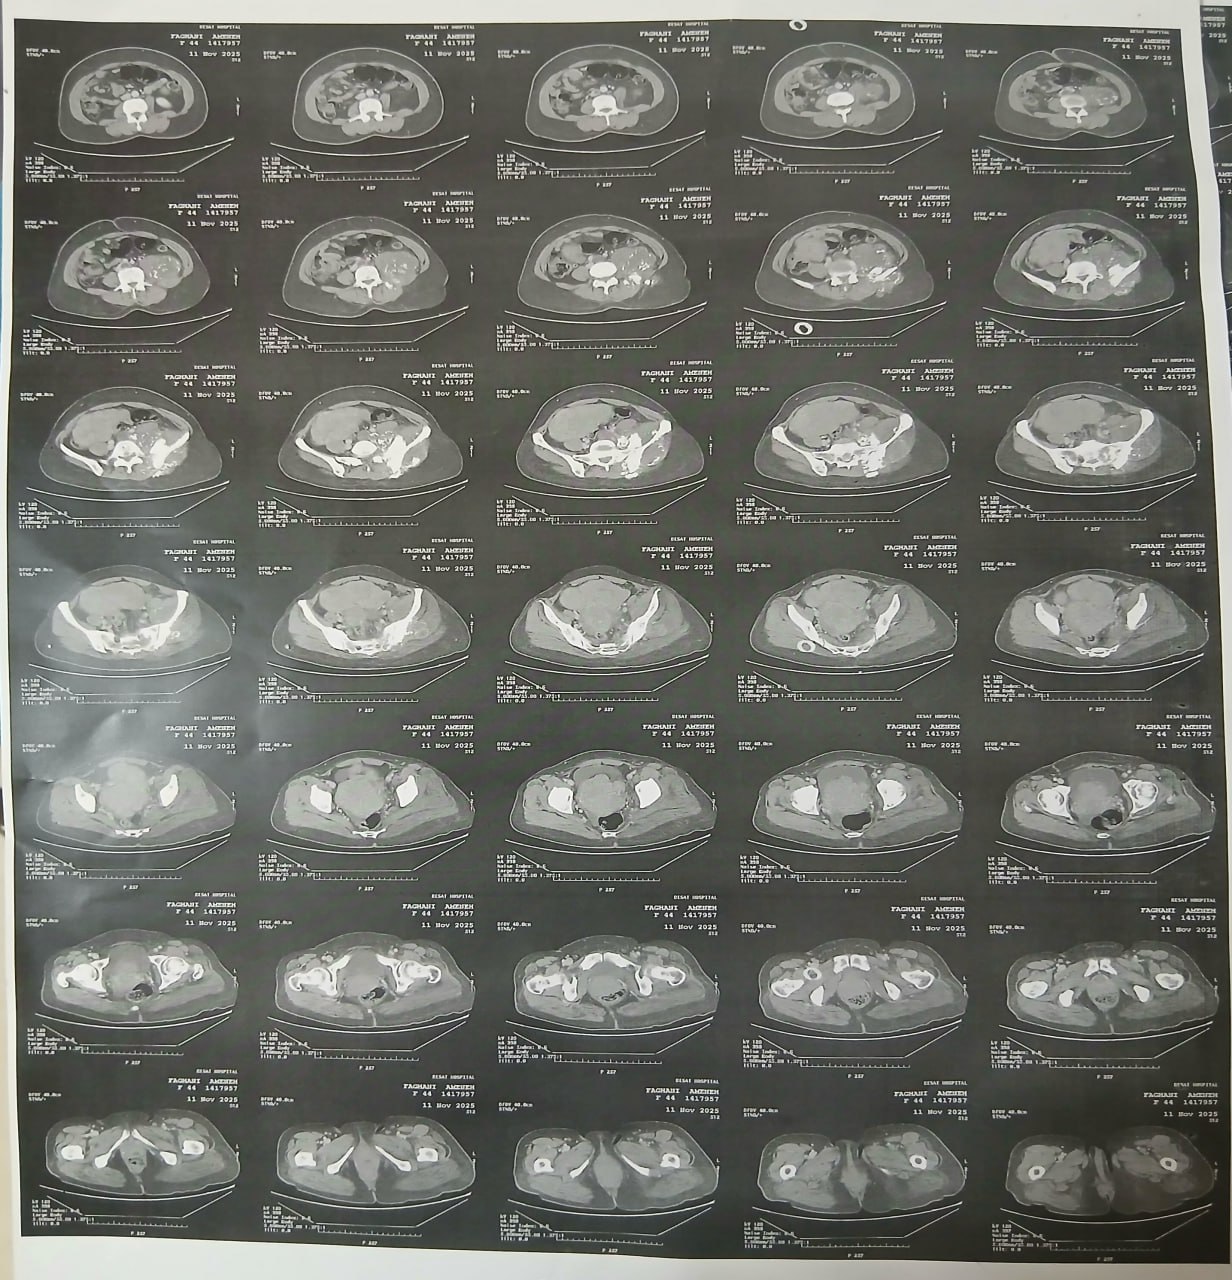

در بررسیهای تصویربرداری (MRI)،در تاریخ 24.7 ، تودهای با تشخیص کندروسارکوما همراه با DVT گزارش شده است. بیمار سابقه درد لگن داشته که شدت آن در حال حاضر نسبت به گذشته کاهش یافته است. به گفته بیمار، حجم توده در ابتدا در حدود اندازه یک تخممرغ بوده که در حال حاضر کاهش یافته است. همچنین تورم اندام تحتانی در حال حاضر نسبت به قبل کمتر شده است.

مراجعه کرده است. پس از بررسی های انجام شده در MRI انجام شده توده با درگیری مفصل ساکروایلیاک چپ و DVT؛ ابتدا تحت درمان DVT قرار گرفته است و سپس جهت پیگیری تومور رویت شده تحت بیوپسی قرار گرفته است و با تشخیص کندروسارکوما به این مرکز مراجعه کرده است و تحت کموتراپی و رادیوتراپی قرار گرفته و سایز تومور کاهش یافته است.

(تصویر مربوط به این مراجعه نیست) Other: